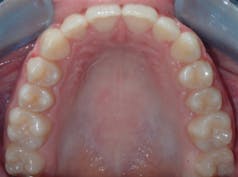

Case 1: 27-year-old male: 2-year clear aligner treatment. There was an estimated 8 mm to 10 mm increase in the transverse measurement. Case and photos courtesy of Dr. Daniel Noor.

Case 2: 48-year-old female: 15-month clear aligner treatment. This case demonstrates an improvement in a remodeled alveolar complex and an increase in vertical dimension. Case and photos courtesy of Dr. Ben Miraglia.

Before: V-shaped arch. After: U-shaped arch.

Before: Severe deep bite. After: Improved vertical dimension.

Before: V-shaped arch. After: U-shaped arch; implant placed No. 14.

Case 3: 17-year-old male: 1-year treatment. Expanding and proclining delivered more room for the tongue and increased oral cavity volume without IPR or extractions. Case and photos courtesy of Dr. Ben Miraglia.

Before: V- and omega-shaped arch, crossbite. After: U-shaped arch, no IPR, no EXT, increased oral cavity volume.